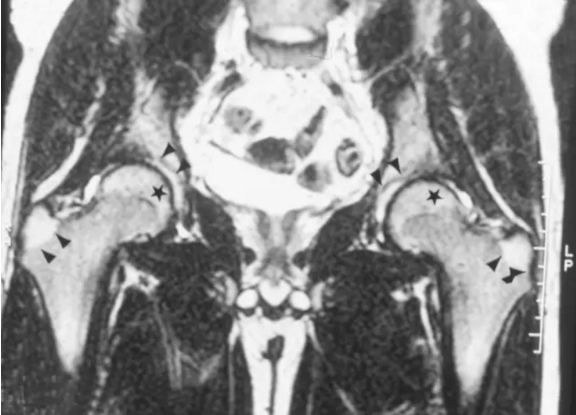

脂肪髓出现在股骨头骨骺及2岁以上的所有个人的大转子。脂肪骨髓在T1加权图像(T1WI)和T2加权图像(T2WI)上具有高信号强度(参见下图)。当存在造血骨髓时,其存在于股骨颈,转子间区域和髋臼中。它在T1WI上具有低信号强度,在T2WI上具有高信号强度(参见下图)。

冠状T1加权磁共振图像显示在股骨颈近端的低信号和表示造血骨髓的转子间区域(箭头)。

冠状T2加权磁共振图像显示在近端股骨颈和转子间区域内的低信号,代表造血骨髓。增加的信号在大转子(单箭头)和股骨头骨骺(星)区,代表正常的脂肪骨髓。正常的髋关节(双箭头)含有少量的流体。

髓质腔在从股外侧的下外侧延伸到股骨头的超内中侧的所有成像序列上包含低信号的突出的垂直定向的线性条纹。这些代表负重小梁并且类似于在CT扫描上看到的射线样改变(参见上面的2个图像)。髓腔由边缘尖锐的低信号强度的包绕,其代表骨的皮质。皮质和小梁具有弱的MRI信号强度,因为低浓度和氢离子的移动性降低(参见上图2)。代表关节软骨的高信号强度的细线围绕股骨头的外边缘。 曲线低信号线,代表骨髓,横向的股骨颈骨髓横向内侧(见上图2)。 与髋臼相邻的髂骨的髓腔与股骨头相比具有稍微更低和更不均匀的信号强度(参见上面的2个图像)。